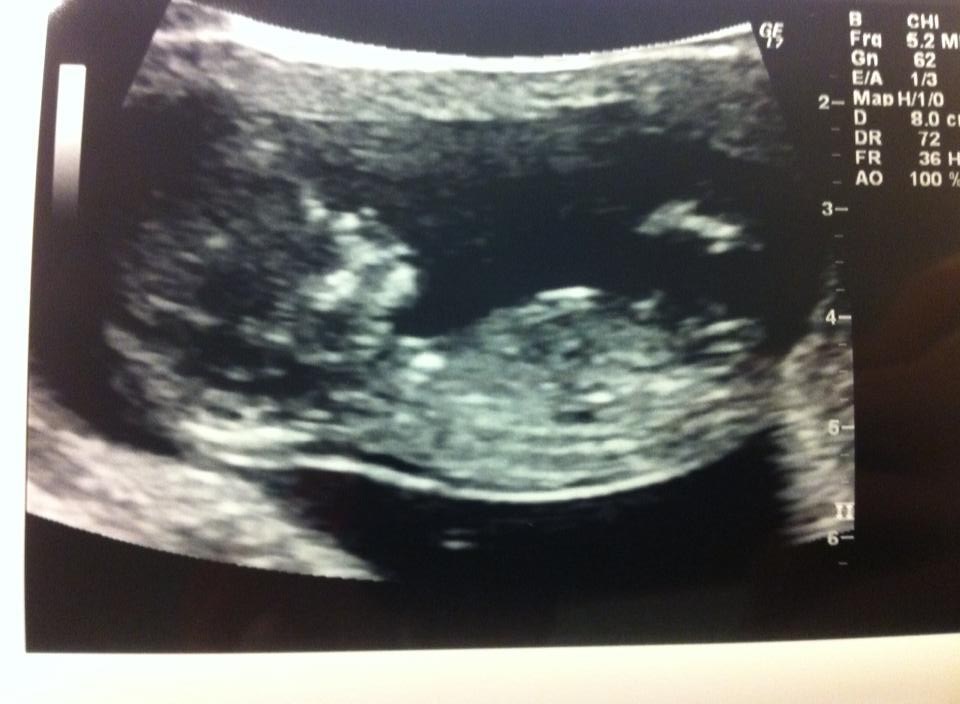

gud ... denne dag har jeg bare ventet på i 2 år og 6 måneder... og ENDELIG kom dagen hvor jeg kom til nakkefoldsscanning, og fik svaret på doubletesten og selve væskemængden i nakkefolden.. og den var som den skulle være på

1:3177 så det var bedre end hvad jeg egentlig havde håbet på..

Blob/blyp var dog svar at få til at ligge stille så scanningsdamen måtte ryste hele min mave for at den gad ligge i den position som den skulle ... hihi det squ komisk og se hvordan den hopper rundt derinde i sin svømmepøl

også kan den åbenbart godt lide at ligge med begge arme bag hovedet, og rigtig fede den

og så lige et vellykket billed denne gang